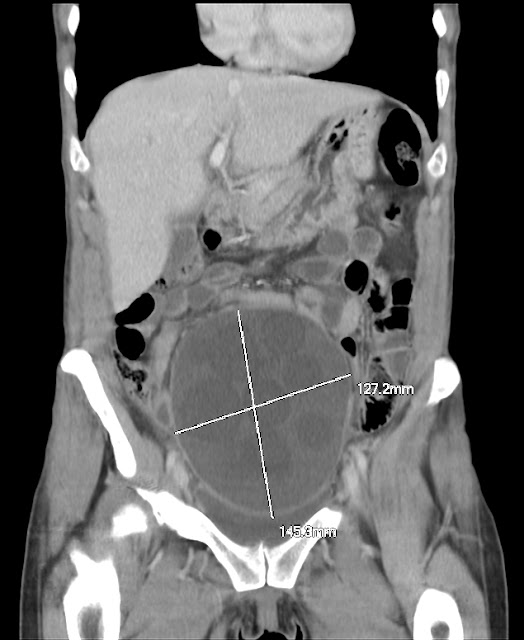

• Pseudoquiste abdominal. Es una colección líquida intraabdominal, loculada, que se desarrolla en el peritoneo.

Rx del abdomen mostrando la integridad del cateter intrabdominal

y su correcta situación sin complicaciones